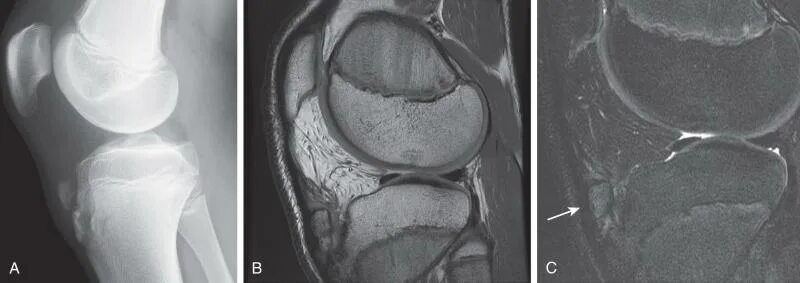

Код мкб шляттера